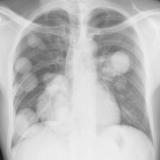

Nodules & Masses

Album: Nodules & Masses

Date: 01/25/2006

Size: 37 items

Views: 60462